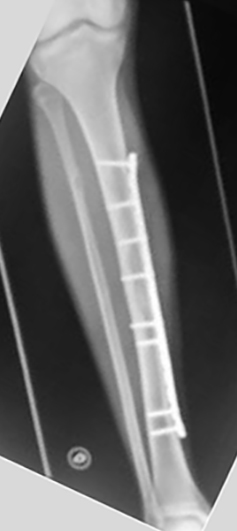

Se utilizaron placas bloqueadas LCP (Synthes, Paoli, PA) en seis pacientes y en dos pacientes placas de reconstrucción bloqueadas (Synthes, Paoli, PA) acorde al largo del hueso (placas largas). En una primera instancia se colocaron fijadores externos en las fracturas expuestas de seis pacientes. Se realizaron limpiezas quirúrgicas en promedio de 2 por paciente (rango: 1-5) y una vez que las partes blandas lo permitieron, se colocó la placa bloqueada. El tiempo promedio para la realización de la cirugía definitiva fue de 8 (rango: 3 - 25) días. En cuatro pacientes se realizó un abordaje antero-interno y se colocó la placa en el sector interno. En dos pacientes se realizó un abordaje externo y se colocó la placa en dicho sector. En otros dos pacientes se realizó un abordaje externo proximal y otro anterior distal, deslizándose la placa desde el sector externo al sector anterior, previo contorneado de la paca. Solo se pudo realizar la técnica MIPO en dos pacientes.

Del total de pacientes, cuatro tuvieron resultados excelentes y cuatro satisfactorios. Todas la fracturas consolidaron en un tiempo medio de 15 semanas (rango: 12-21). Se realizó solo aporte de injerto de esponjosa en un paciente con una pseudoartrosis atrófica tratada previamente con EEF. Todos los pacientes presentaron una movilidad completa de la rodilla y cuello de pie indolora, sin manifestar alteraciones de la marcha y no se encontraron deformidades angulares (mediante examen clínico y radiografías) ni discrepancias en los miembros inferiores significativas con un promedio de hipercrecimiento de 1,6 (rango: -5 a 10) mm. Se autorizó el apoyo parcial a las 5 semanas (rango: 4-8 semanas) y el apoyo total a las 10 (rango: 8 – 13) semanas. Como complicaciones menores, cuatro pacientes presentaron dolor en el implante, sobre todo en aquellos pacientes donde se colocó la placa en el sector interno y en la configuración externa / anterior, sin significado funcional, coordinándose para retirar las mismas (Tabla 1) (Tabla 2) (Figura 1) (Figura 2).